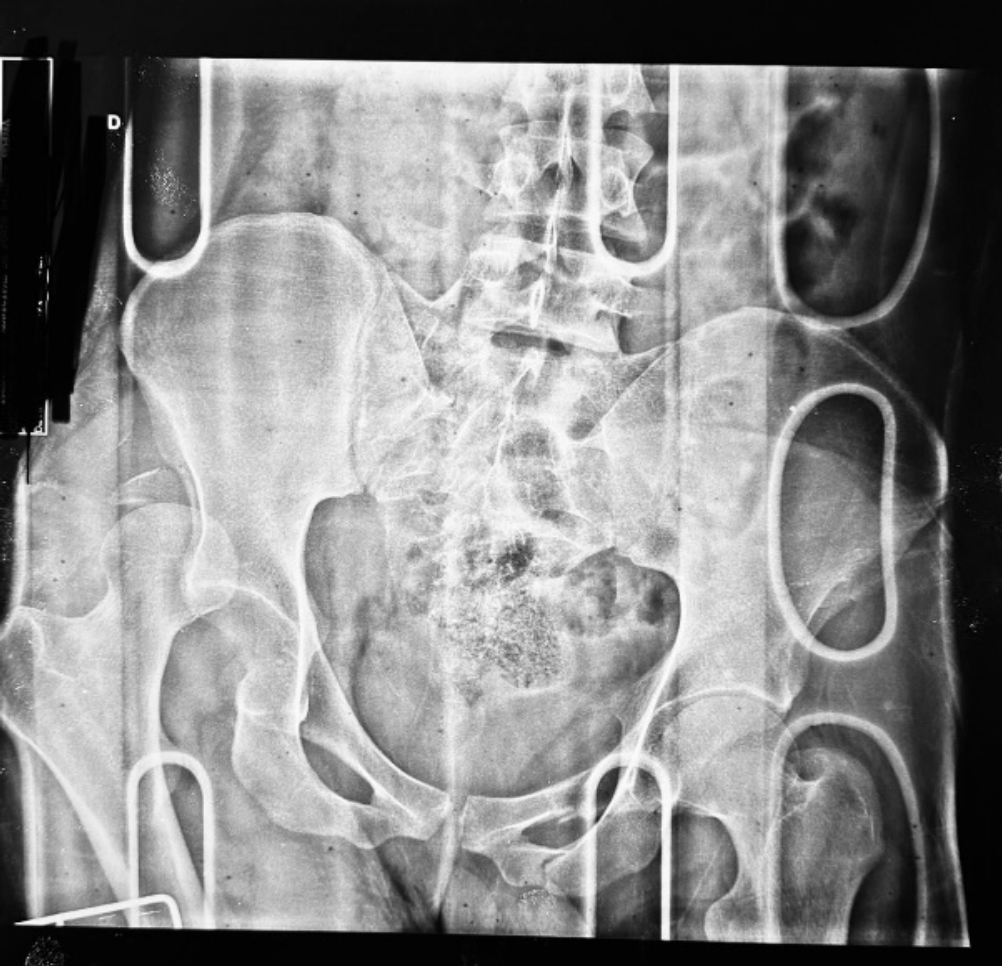

Paciente masculino de 20 anos, natural da Colômbia e residente em Porto Velho, Rondônia, sofreu uma colisão entre motocicleta e automóvel, sendo arremessado contra um muro. Na admissão, cinco horas após o acidente, radiografias revelaram luxação coxo-femoral posterior direita, luxação posterior de joelho direito (Figura 1), fratura do anel pélvico (Figura 2) e fratura diafisária da tíbia direita (Figura 3), além de lesão neurológica no membro inferior, sem comprometimento vascular.

Figura 2 – Radiografia de Bacia

Descrição: Radiografia AP de bacia realizado no PS pós trauma, visualizando fêmures proximais com solução de continuidade em ramos ísquio-púbicos esquerdo, fratura da asa sacral direita, luxação posterior de quadril direito associado a fratura da parede posterior do acetábulo ipsilateral.

Fonte: Banco de dados do Hospital de Base Dr. Ary Pinheiro – HBAP.